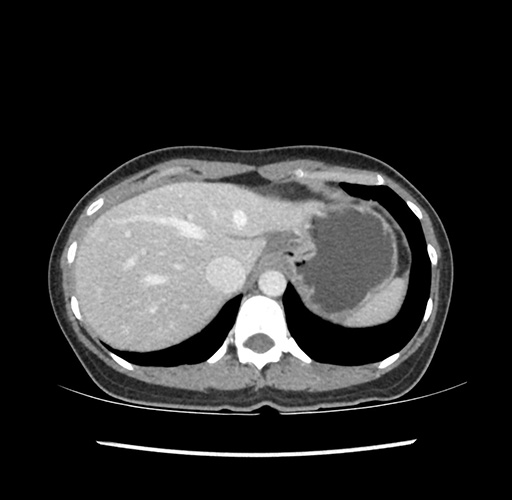

Imaging Analysis

Look through the patient's CT scan to identify any areas of concern for the necessary procedure.

Based on your CT findings, which issue(s) would give reason for "planned slowing down moment(s)" in this case?